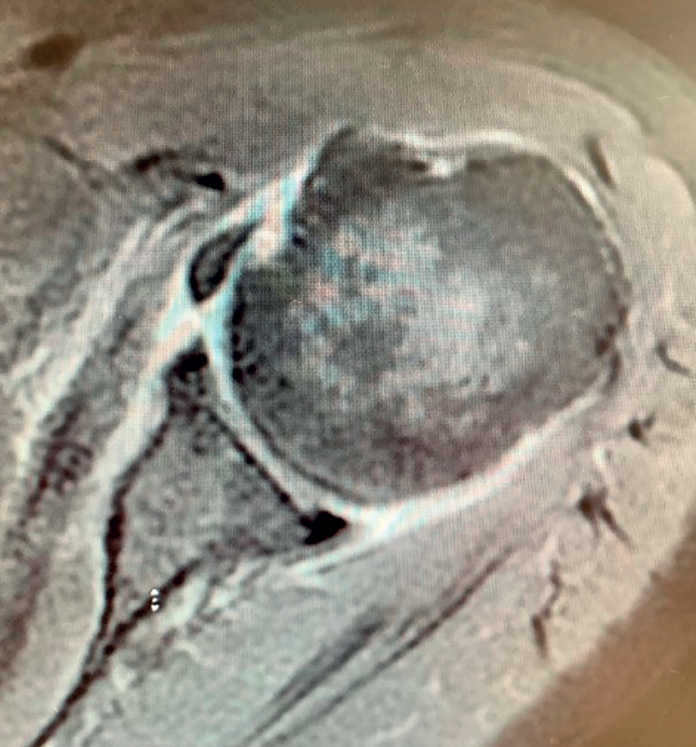

Boileau in 2005 or Simovitch in 2007(28,32) concluded that reverse replacement is unable to secure the restoration of external rotation. In many patients, only the teres minor will be able to afford active external rotation. If the teres minor presents rupture, retraction or adipose degeneration (which can be assessed by magnetic resonance imaging or computed tomography), we can predict a poorer outcome in these individuals, with an external rotation deficit(33,34). The lack of external rotation may prove quite disabling, especially in patients that use the arm in abduction. For this reason, some investigators such as Longo, in 2011(35), indicate the possibility of latissimus dorsi transfer to the reverse replacement implant, to restore external rotation in the patient.

Reverse shoulder replacement shifts the center of rotation distal and medial (Figure 5), increasing the lever arm of the deltoid muscle and recruiting more anterior and posterior fibers of the muscle, improving its function in patients without rotator cuff(1,19,20). In general, the patients can be expected to show increased anterior flexion and abduction of the shoulder. Having greater or lesser external rotation will depend on the quality of the teres minor and infraspinatus, among other factors (Figure 4). With regard to internal rotation in patients with reverse shoulder replacement after massive rupture, the results are less predictable and are conditioned by the implant design and the characteristics of the patient, among other factors. We must know the functional limitations of the implant and inform our patients about the results that can be expected.